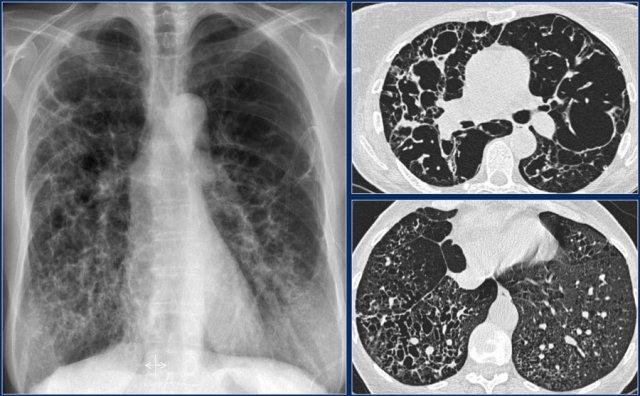

Đây là một trường hợp khác.

Phim X-quang ngực thẳng cho thấy kiểu hình ảnh mô kẽ dạng lưới với ưu thế ở đáy phổi.

HRCT cho thấy tổ ong hóa và giãn phế quản do co kéo.